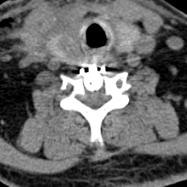

颈椎CT显示C6/7平面增生的骨赘占据椎管,压迫脊髓